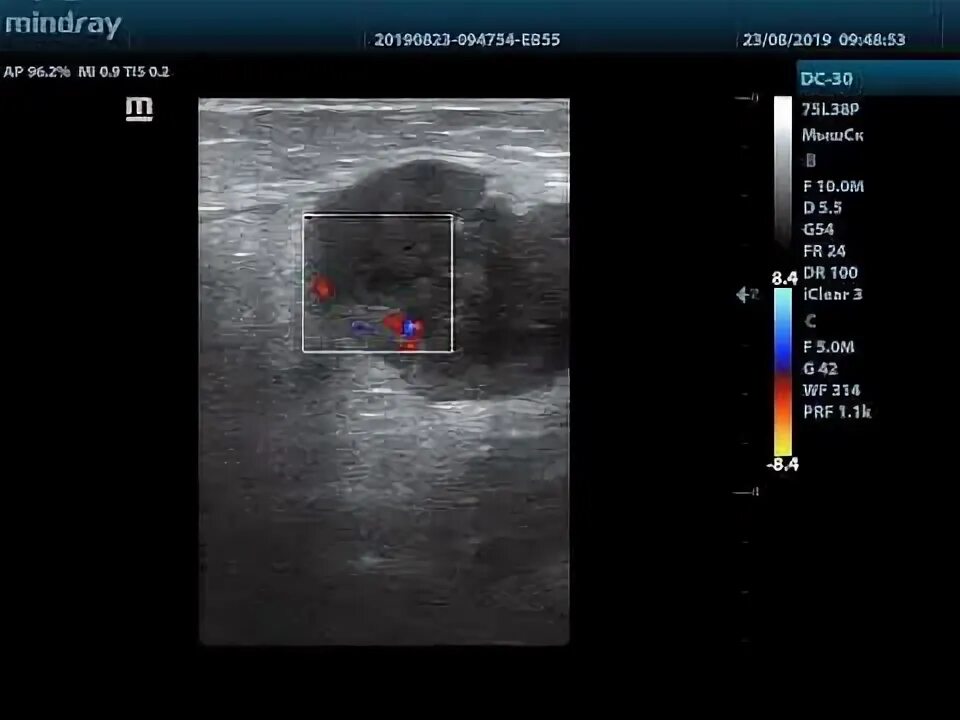

Метастазы в паховых лимфоузлах